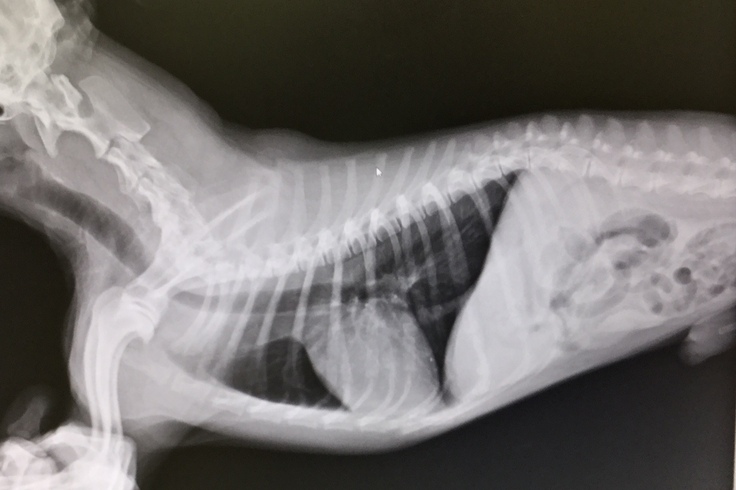

こちらは9月11日の心臓検査の診察結果です。写真を比較していただくと、心臓が大きく肥大しており気管を圧迫しているのが分かります。

僧帽弁閉鎖不全症で肥大した心臓

肥大したろんの心臓

↑10月8日の心臓の検査でさらに心臓が肥大している事が分かりました。